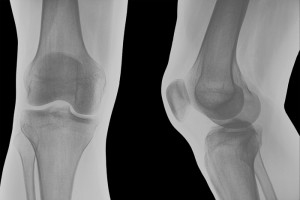

X-Rays

X-rays remain the most important imaging method for determining the severity of your arthritis or the cause of bone pain. Though x-rays show only the position of the bones, the space between bones is an accurate reflection of how much healthy cartilage remains. Narrowing of this space over time is associated with loss of cartilage and can be used to monitor the further advance of osteoarthritis and rheumatoid arthritis.

OA and RA look quite different on x-rays. With RA, small erosions or destruction of the bone can be seen, as can thinning of the bones around the joints (periarticular osteopenia). With OA, you will see tiny irregular outgrowths or bone spurs (osteophytes).